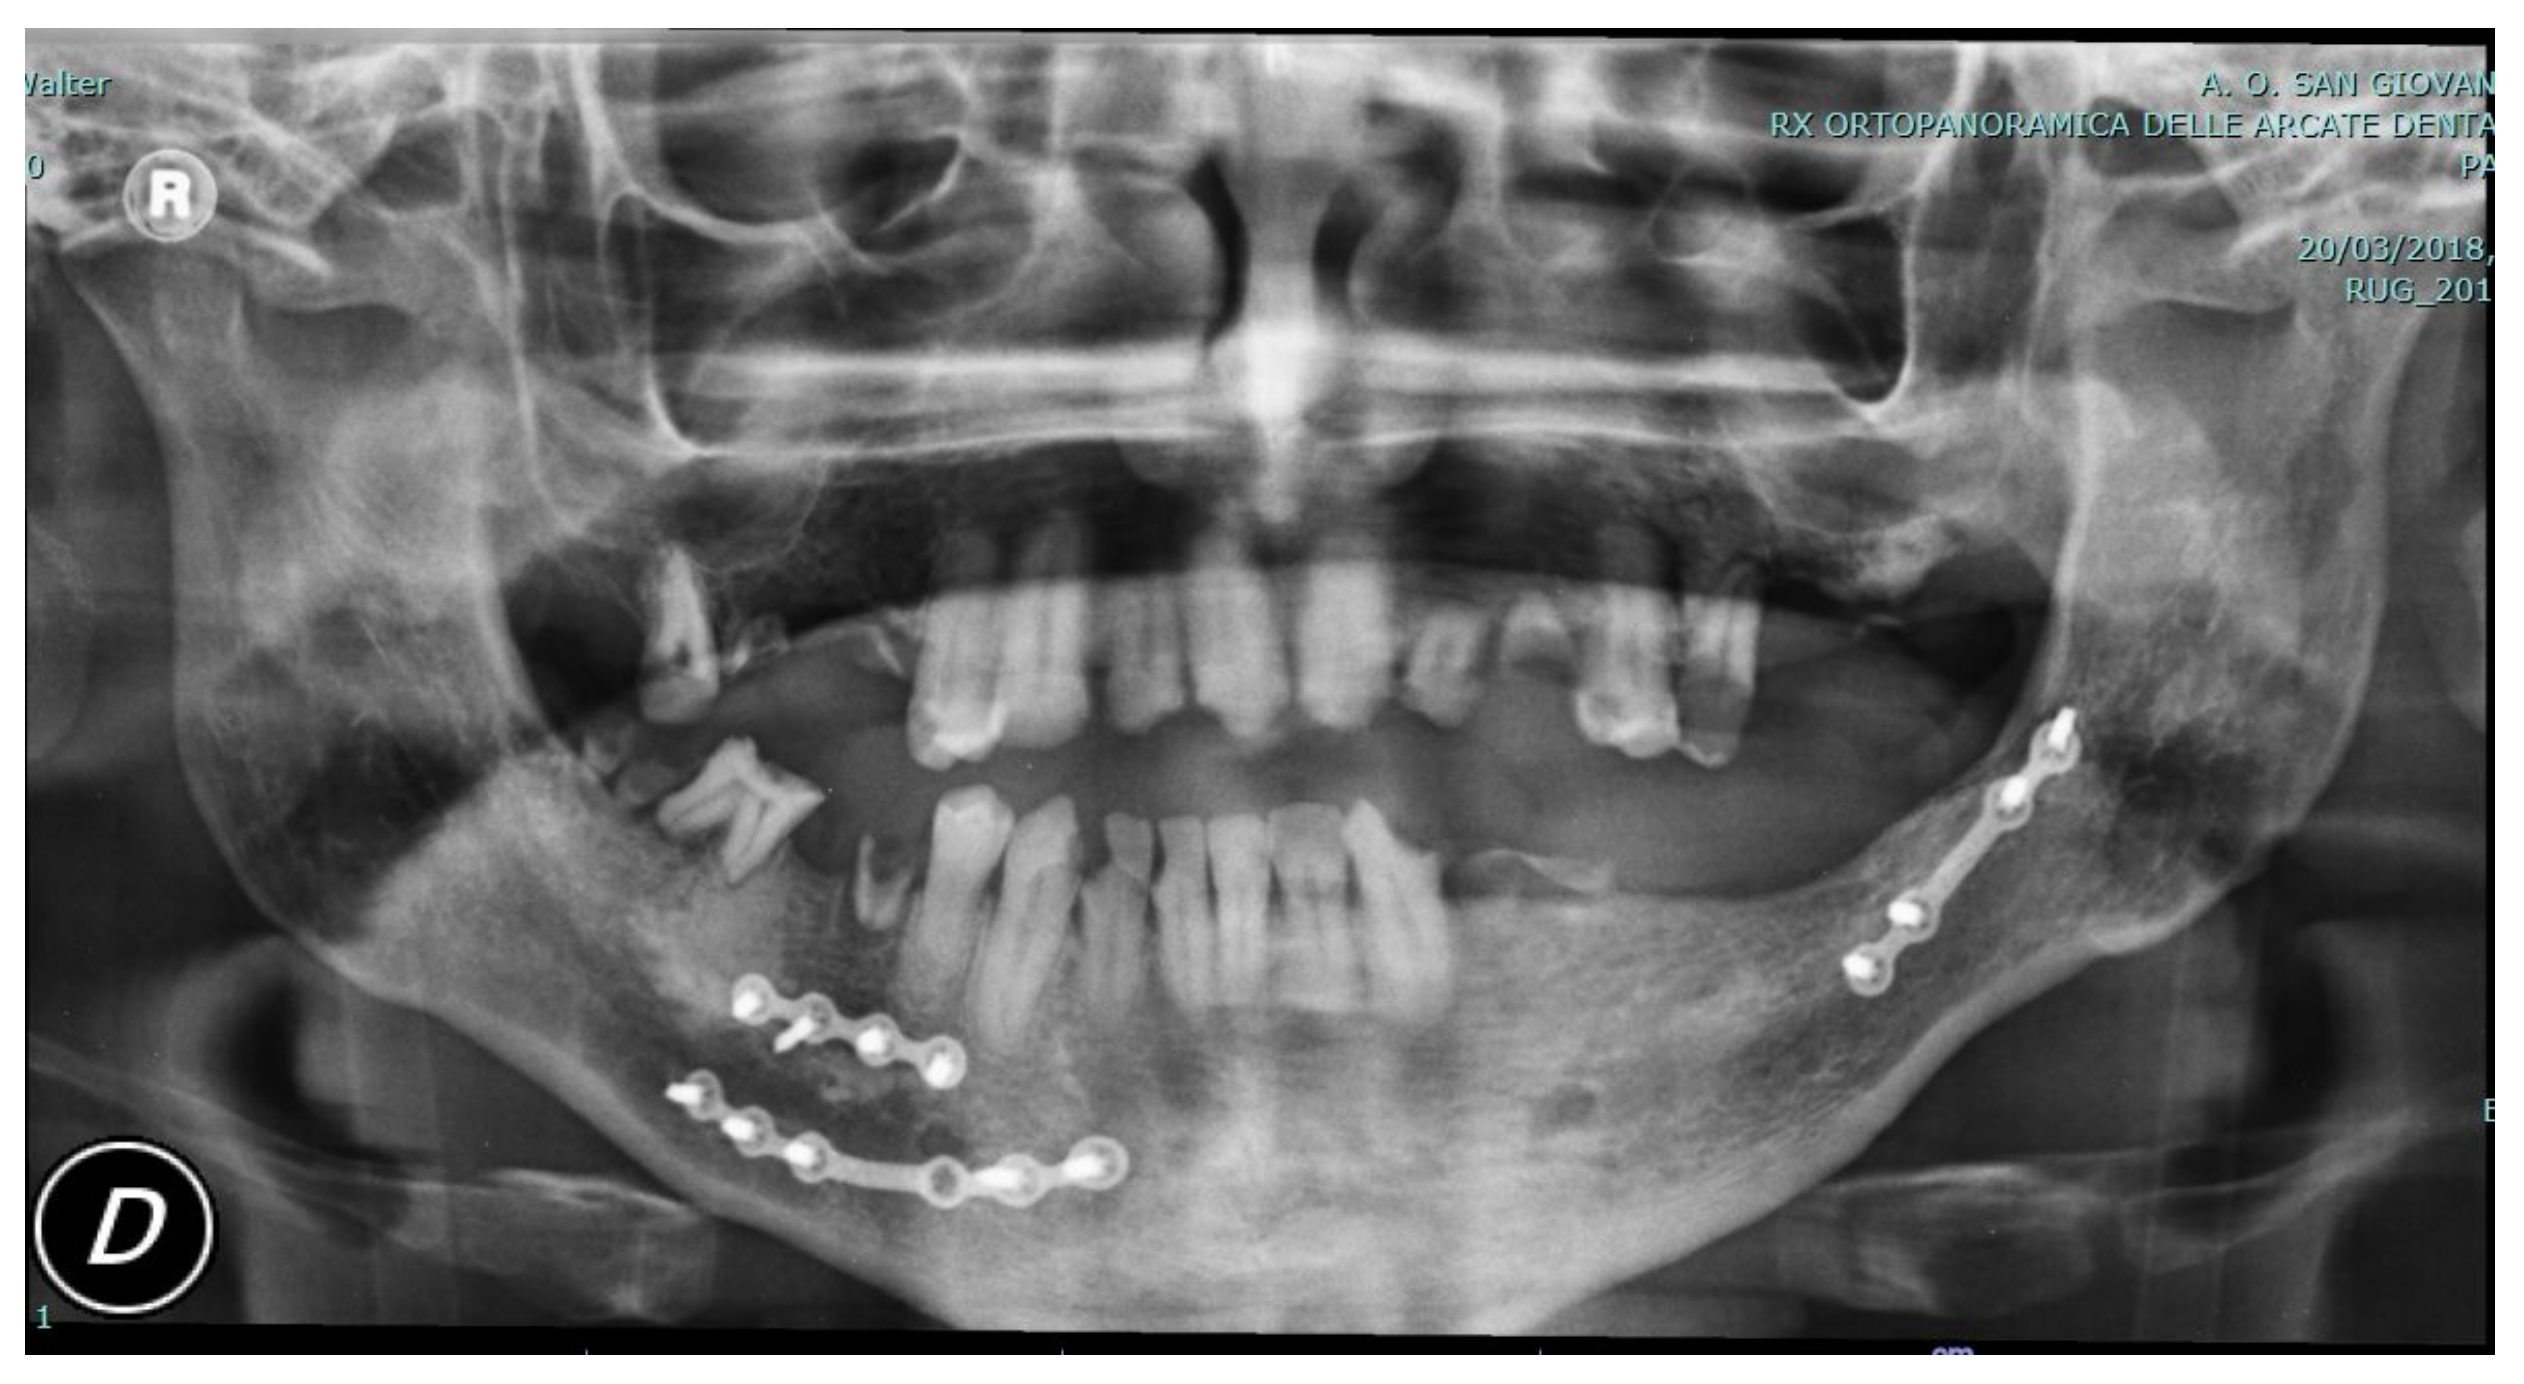

In the following figures, the medical images, orthopanoramic images (Figure 6 and Figure 7) before and after an orthognathic surgery, the implanting screws (Figure 8), and a digital reconstruction (Figure 9) are shown.

Figure 7. Post-operative view showing personalized CAD/CAM plates after the previously installed plates removal and orthognathic surgery class III correction.